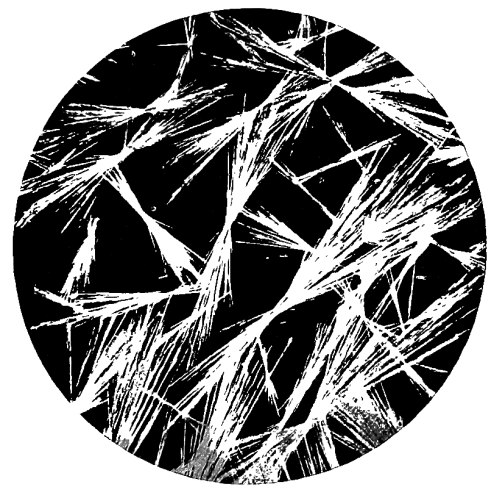

28. Photo-micrograph of Crystals of Oxalic Acid 258

29. Photo-micrograph of Crystals of Oxalic Acid 259